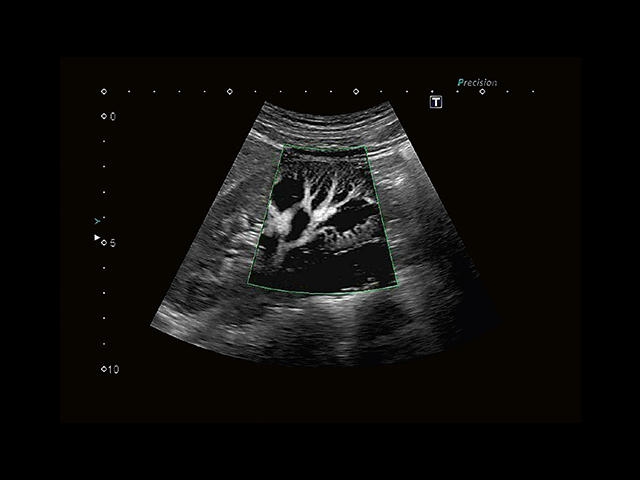

• Fly Thru. Виртуальная эндосонография обеспечивает построение трехмерной модели полостей, протоков и сосудов в рельном времени, облегчает организацию инвазивных процедур и динамических исследований. Посредством Fly Thru можно установить шунты и стенты, проводить точные оперативные вмешательства.